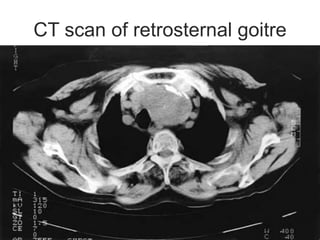

CT scan of retrosternal goitre

CT scan ofretrosternal goitre